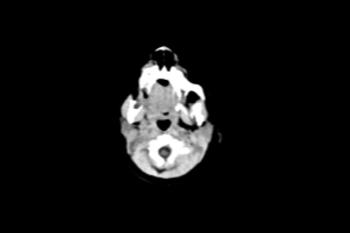

Figure 4. Images obtained in the case of an 18-year-old woman, first seen for rash at 10 weeks of pregnancy, with confirmed Zika virus infection. US findings obtained at 20 weeks of gestational age were reportedly normal, with normal head circumference of 17.5 cm. At 37 weeks of gestational age, (a) sagittal transvaginal and (b) coronal transabdominal US images obtained with the head upside down show a small head circumference (26.4 cm, corresponding to 28 weeks 5 days, below the 3rd percentile), moderate ventriculomegaly with dense intracranial calcifications (arrowheads on a), and abnormal head shape with flattened appearance and thickened skin (arrow on a). On the sonogram, it is difficult to precisely localize the calcifications, given the thin parenchyma. (c, d) Axial bone window CT images, (e) sagittal localizer CT image, and (f–h) axial CT images show microcephaly with cerebral atrophy, and, despite ventriculomegaly, the extra-axial cerebrospinal fluid spaces are still prominent. The hypoattenuating calcifications are predominantly located in the subcortical white matter at the gray matter–white matter interface. There is markedly abnormal skull shape with some eversion of the bones at the suture sites (particularly frontoparietal sites), with redundant skin folds (particularly in the parieto-occipital region). (i) Sagittal T1-weighted, (j, k) coronal T2-weighted, and (l) axial susceptibility-weighted MR images obtained at 1 month of age show an undersegmented midbrain, severe microcephaly, open sylvian fissures, and polymicrogyria. The dense calcifications are evident on the susceptibility-weighted image. On the sagittal images (a, e, i), note the small supratentorial compartment and associated skull deformity.

High-res (TIF) version